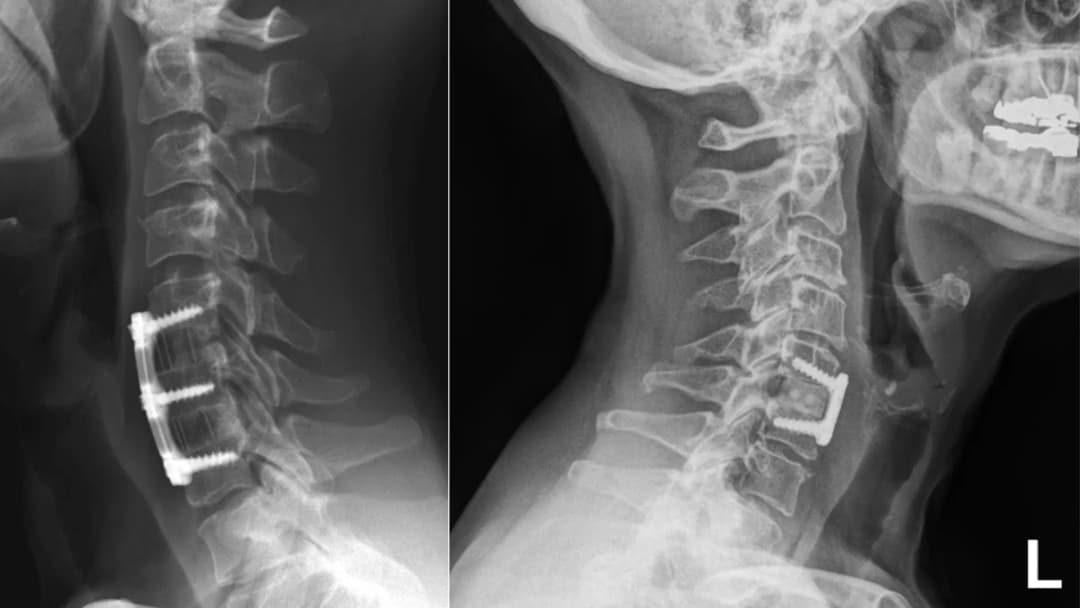

During the procedure, the surgeon makes an incision in the front (anterior) of the neck to access the spine by delicately working around the important structures contained in the neck. They then carefully remove the damaged or herniated disc that is compressing the nerves. After the disc is removed, the space between the vertebrae is filled with a special cage made of titanium or bone graft. This acts as a bridge, promoting a fusion, where the two vertebrae eventually grow together into a single, stable bone. A small plate and screws are often used to hold everything in place while the fusion occurs. While the bone is healing, a cervical collar is worn to help stabilize the neck and provide comfort for the muscles.

Anterior Cervical Discectomy and Fusion (ACDF)

Anterior Cervical Discectomy and Fusion (ACDF) is a common surgical procedure used to alleviate nerve and spinal cord compression in the neck (cervical spine). By relieving the pressure on the spinal cord or nerve roots, the associated pain, numbness, tingling, or weakness in the arms and hands can resolve.